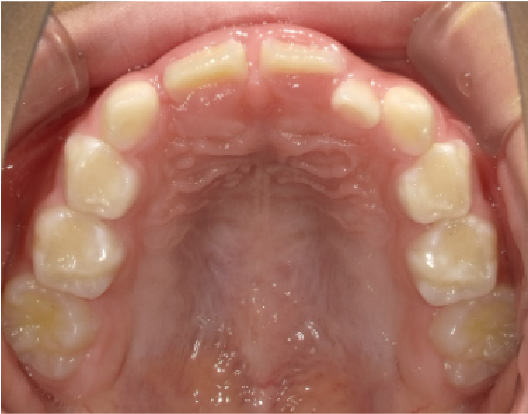

狭い歯列(狭窄歯列)によって、舌が歯列の中に収まらない状態です。

●高口蓋 ●低位舌 ●口呼吸

狭窄歯列(高口蓋)

狭窄歯列(低口蓋)

狭窄歯列(低位舌)

右のように、狭窄歯列だと舌は、狭い歯列に阻まれて、前方や上方の口蓋に自由に動くことができません。その結果、舌は低い位置(低位舌)にあり、前方に出ず後方に位置するので、気道が狭くなってしまっています。

一方、左のように、広い歯列だと舌は、前方にも上方にも自由に動けるので、舌は普段は口蓋についていて鼻呼吸が無理なくできているのです。

狭い歯列(狭窄歯列(きょうさくしれつ))

高口蓋(上顎が深い→鼻腔が狭い)

舌が歯列に納まらない→低位舌

歯並びが悪い

かみ合わせが悪い